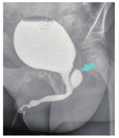

5例患儿年龄为(47.2±42.2)个月,范围在1岁至9岁4个月,中位数为36个月。附睾炎和尿路感染发作3~6次,平均3.8次,中位数4次,附睾炎均为单侧发作。行泌尿系统彩色超声和排尿性膀胱尿道造影检查显示后尿道可见前列腺小囊(图1);患儿尿道下裂术后排尿通畅,最大尿流率(Qmax)为(6.3±1.8)ml/s,中位数为5.6 ml/s。本研究已通过医院伦理委员会审核[伦审(研)2020年第99号],并获得所有参与研究患儿家属的知情同意。